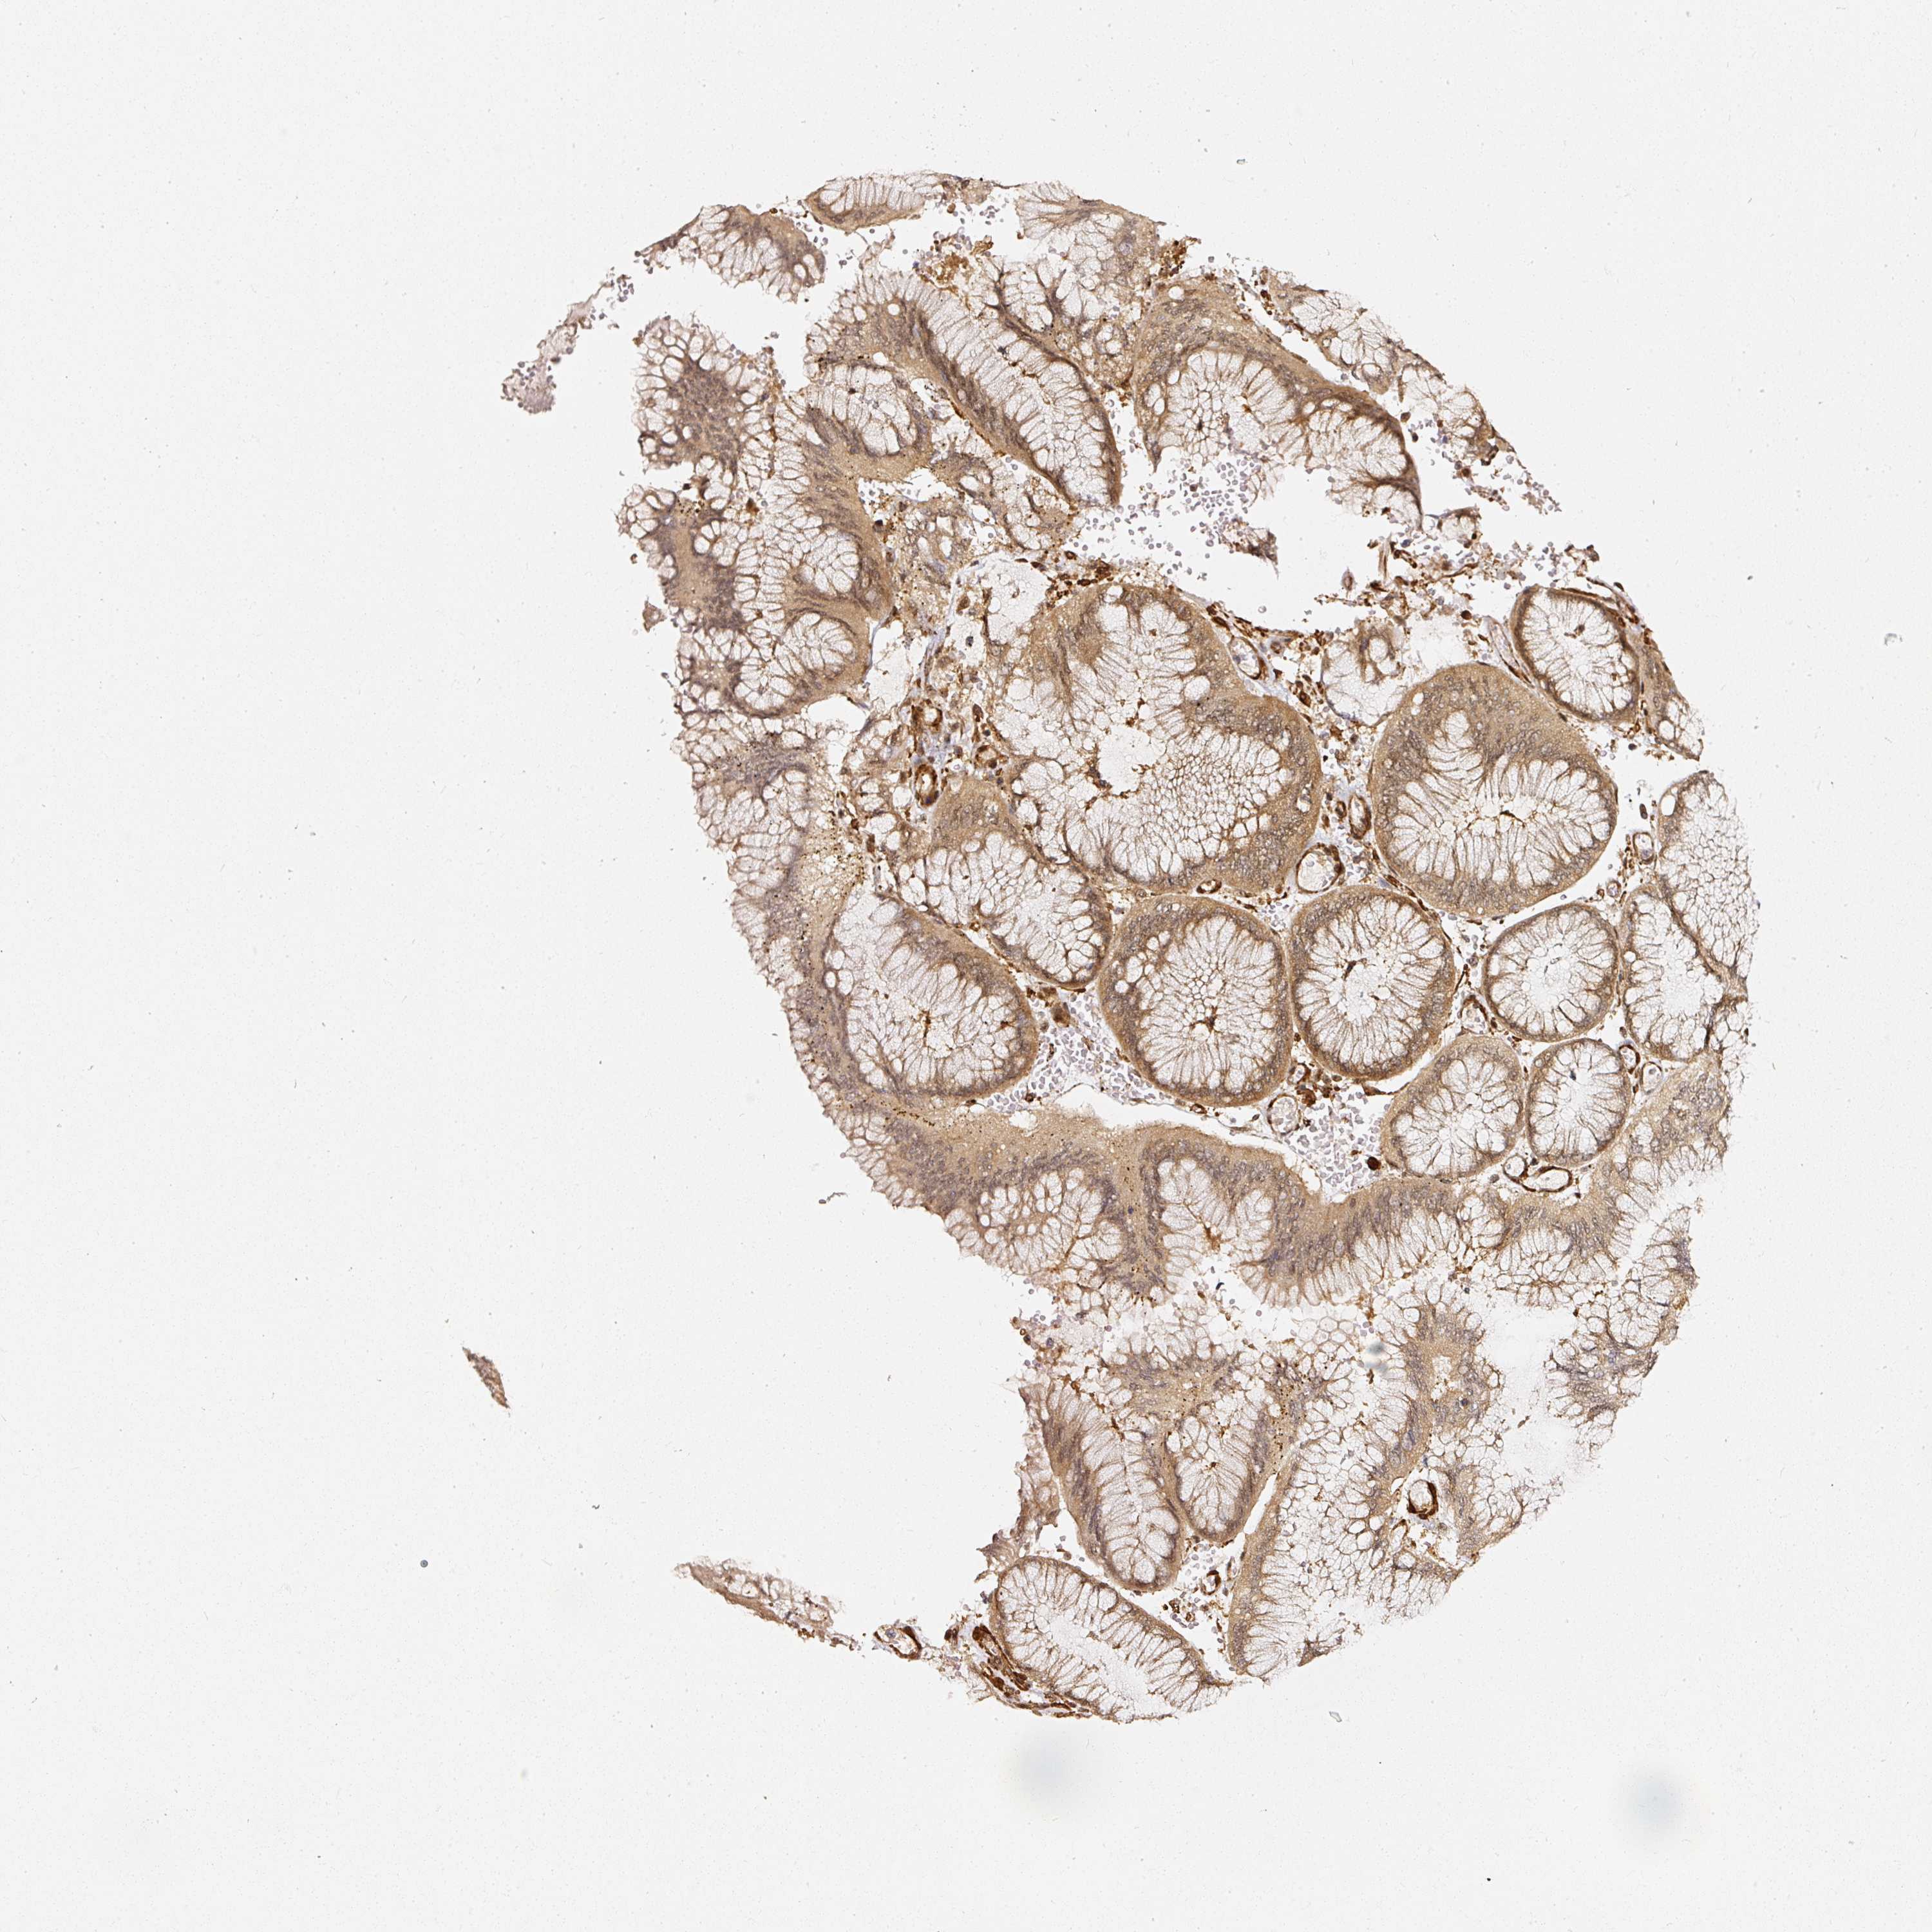

STOMACH CANCER - Protein expressioni

A mouse-over function shows sample information and annotation data. Click on an image to view it in a full screen mode. Samples can be filtered based on level of antibody staining by selecting one or several of the following categories: high, medium, low and not detected. The assay and annotation is described here.

Antibody staining in the annotated cell types in the current human tissue is reported as not detected, low, medium, or high, based on conventional immunohistochemistry profiling in selected tissues. This score is based on the combination of the staining intensity and fraction of stained cells.

Each image is clickable and will lead to virtual microscopy that enables deeper exploration of all samples and also displays staining intensity scores, fraction scores and subcellular localization as well as patient and tissue information for each sample.

Adenocarcinoma, NOS